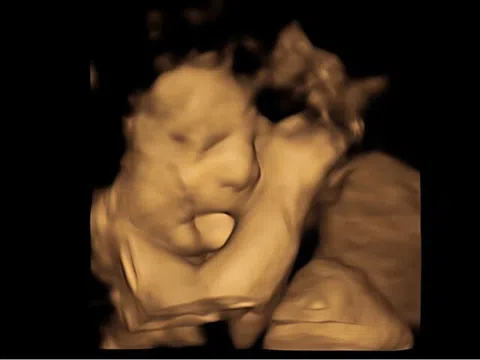

Con gái mang nhiều nét đẹp thừa hưởng từ Kim Na Yoon.